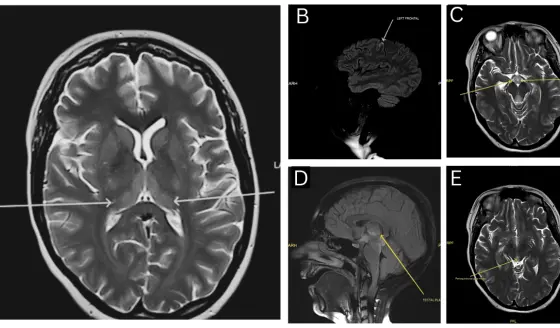

La investigación reveló que la amígdala medial, tradicionalmente conocida por su papel en las respuestas emocionales, funciona como un interruptor maestro para la producción hepática de glucosa.

Los científicos descubrieron un circuito preciso que conecta esta región cerebral con el hígado a través del hipotálamo, estableciendo un canal directo entre las experiencias estresantes y el metabolismo glucémico.